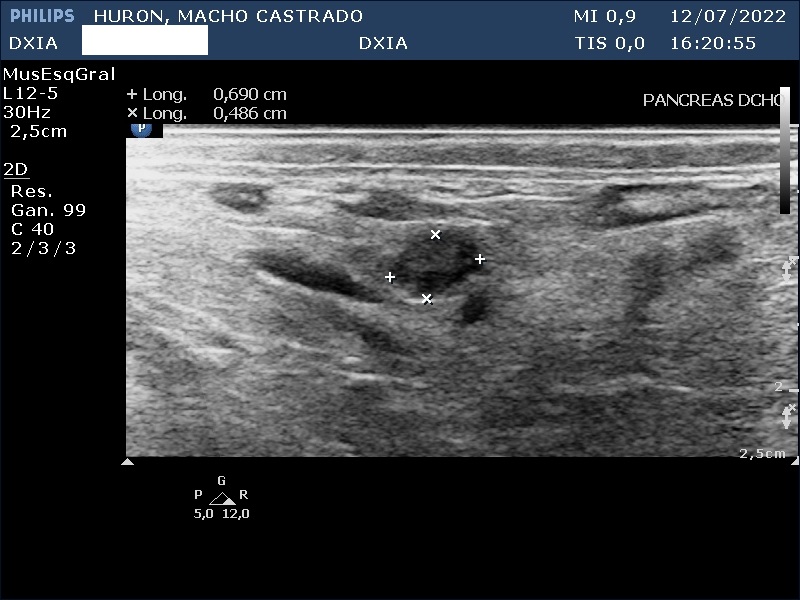

Hallazgos ecográficos